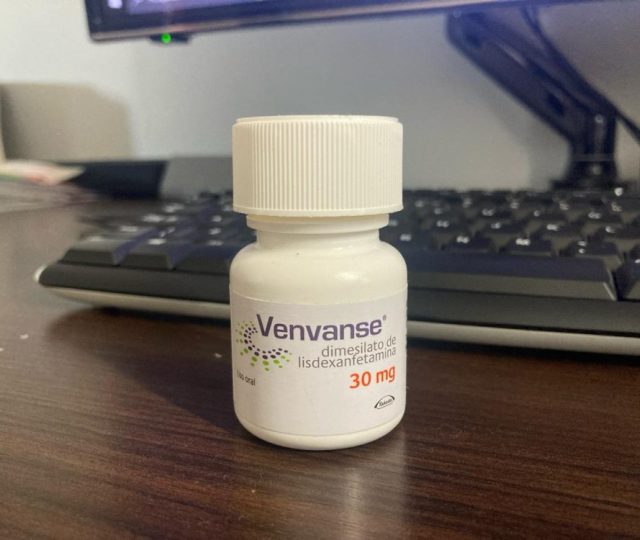

Uma nova esperança surge no horizonte para pacientes com doenças priônicas, graças a um ensaio clínico inovador que está testando uma terapia com oligonucleotídeos antise...